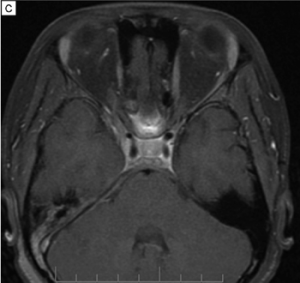

Imaging can aid in diagnosis, especially in cases of orbital soft tissue or EOM involvement, which are better appreciated on orbital imaging. Imaging techniques include CT or MRI of the orbits, and fluorodeoxyglucose (FDG)-PET/CT scan. MRI will demonstrate isointensity on T1-weighted lesions, hypointensity on T2-weighted lesions, and homogenous gadolinium enhancing lesions.[42] FDG-PET scan can be used for systemic evaluation in IgG4-RD, as it can locate distant and/or clinically silent lesions.[43] There are currently no guidelines on how often FDG-PET/CT should be performed.